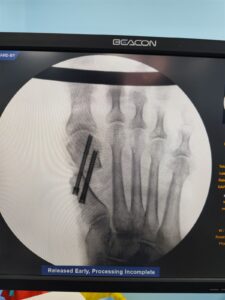

Minimally invasive foot surgery is an advanced surgical technique performed through very small incisions using specialized instruments and imaging guidance. Unlike conventional surgery, MIS reduces trauma to surrounding muscles and tissues, resulting in less pain, minimal scarring, and faster healing.

Accurate diagnosis using modern imaging

Advanced MIS techniques